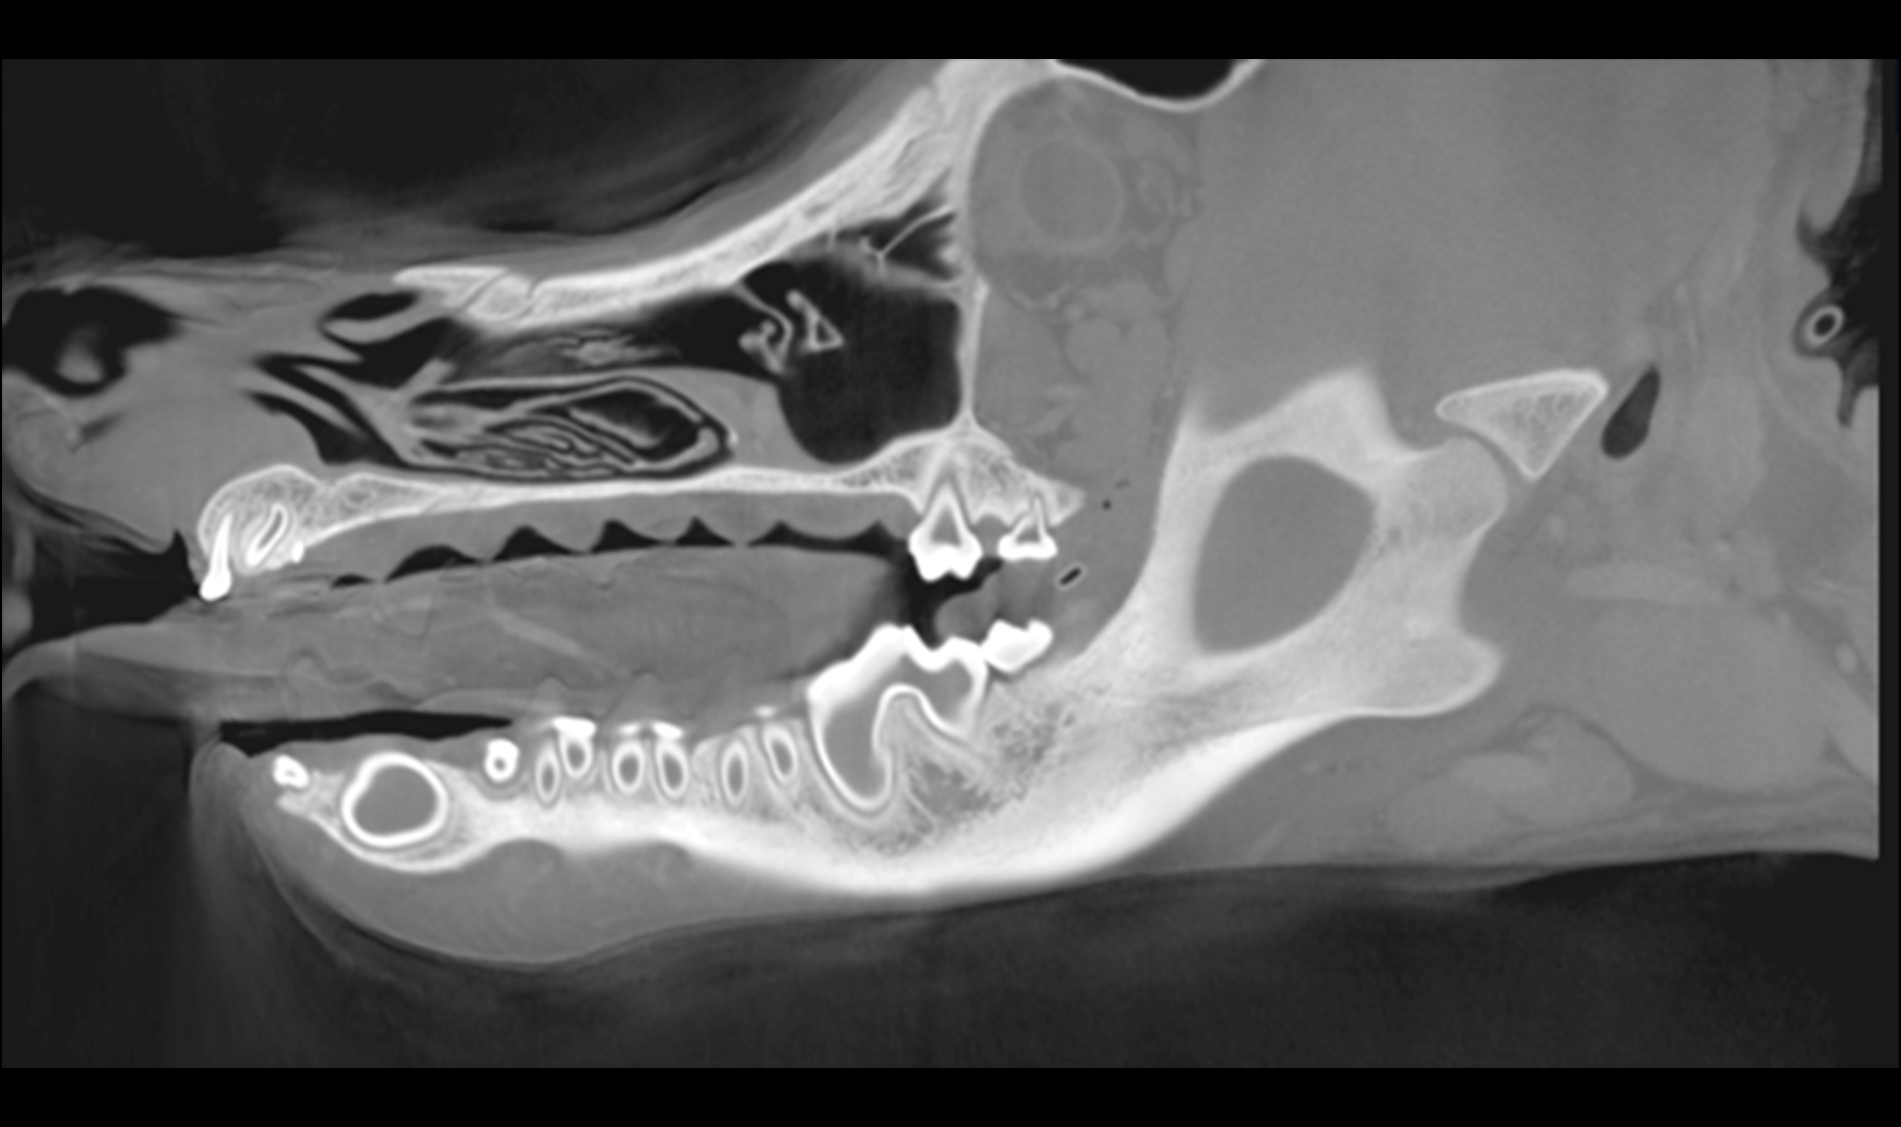

HDVI and HRCT

SPATIAL RESOLUTION

Outstanding image quality in hard tissues.

ISOTROPIC VOXEL

True Multi Planar Reconstruction (MPR) imaging.

NON INTERPOLATED 3D DATA VOLUME REPRESENTATION

Acquisition of volumes with 100% real data: perfect for augmented reality, orthopedics and image-guided procedures.